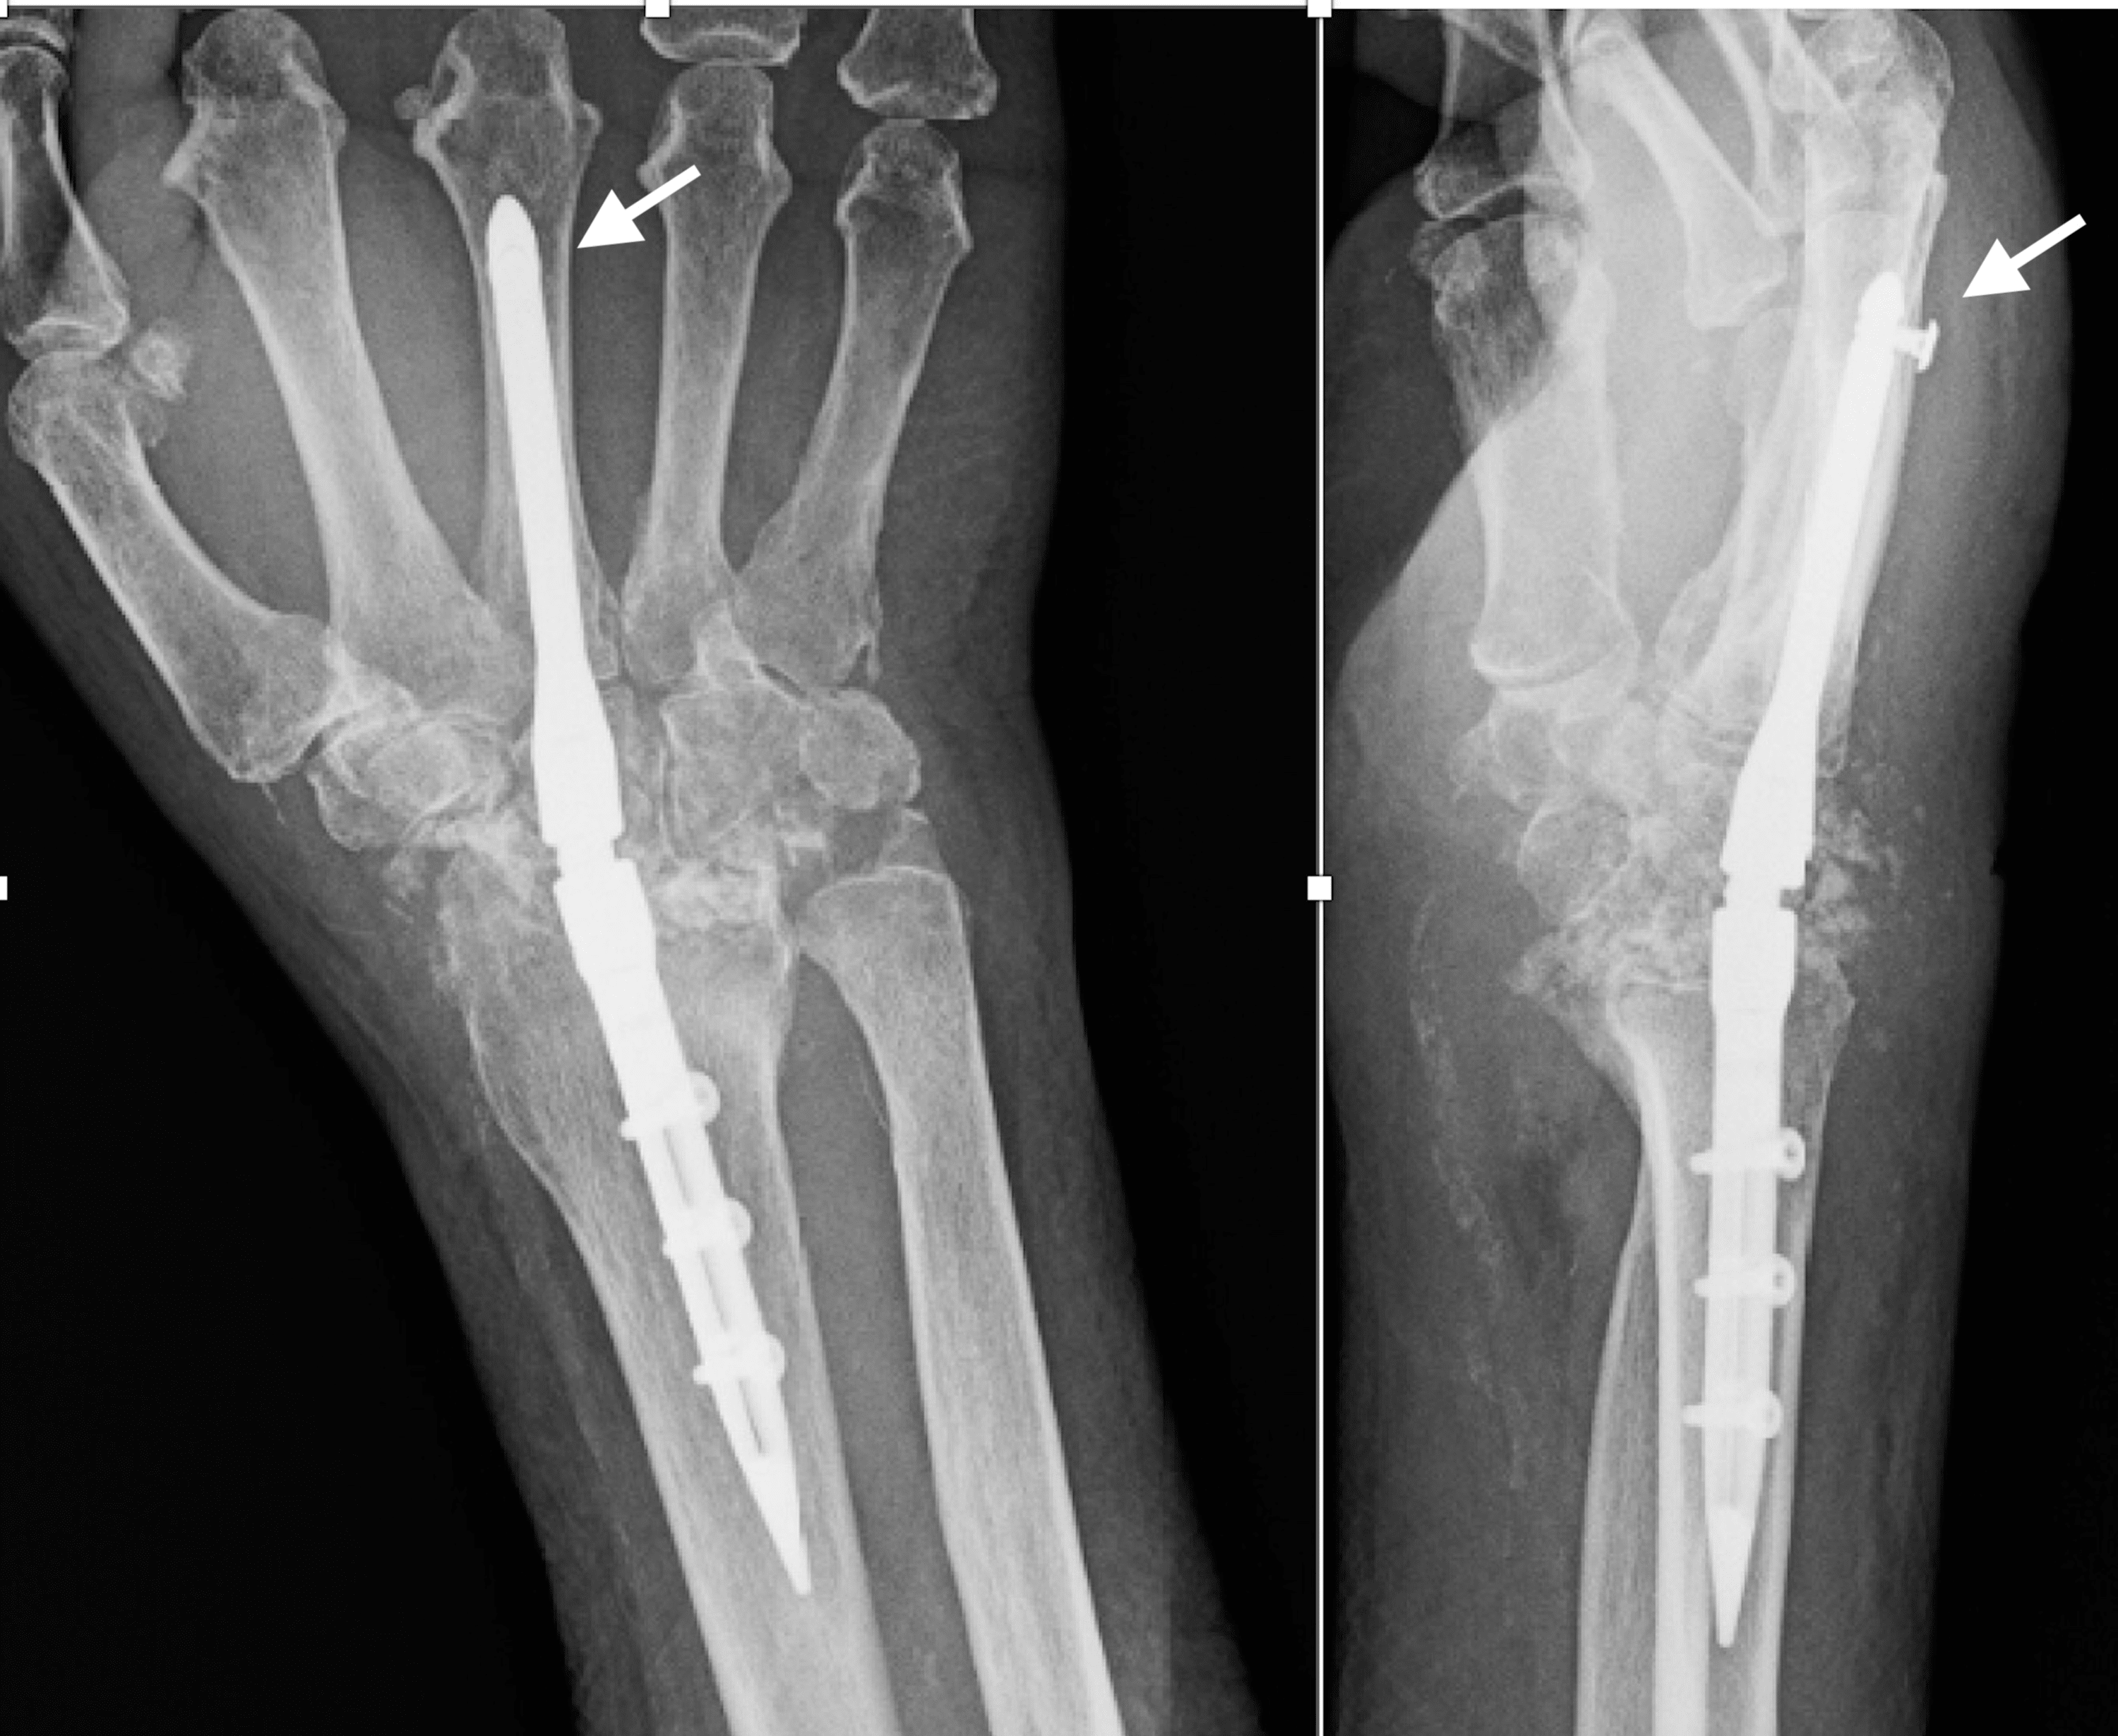

Radiograph of an intramedullary rod antibiotic spacer with significant

Cureus Locked Intramedullary Total Wrist Arthrodesis A Report of Are Intramedullary Rods Removed Background fracture of the femur is one of the most common fractures that, if not stabilized and treated properly, may lead to. Currently, the method most surgeons use for treating tibia fractures is intramedullary nailing. Intramedullary nails used for fixation of femoral fractures may require removal for a variety of reasons. Currently, the method most surgeons use for treating femoral. Are Intramedullary Rods Removed.